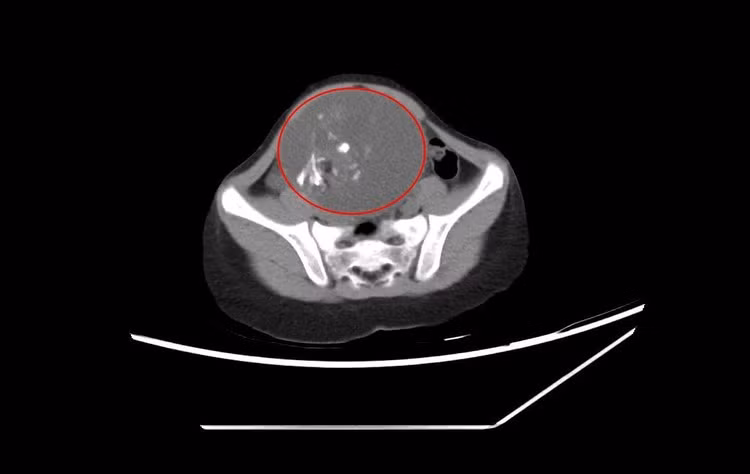

Bệnh viện Đa khoa tỉnh Quảng Ninh cũng vừa bóc tách khối u quái thành công cho bệnh nhi T.N (6 tuổi) ở TP Hạ Long. Theo gia đình, N. ở nhà thường xuyên táo bón, khó đại tiện, thỉnh thoảng thấy bụng có khối cứng khi đói nên đưa đến Bệnh viện Đa khoa tỉnh thăm khám. Kết quả, bệnh nhi khối u buồng trứng 10cm.

Hình ảnh khối u quái buồng trứng 10 cm trên phim chụp – Ảnh BVCC